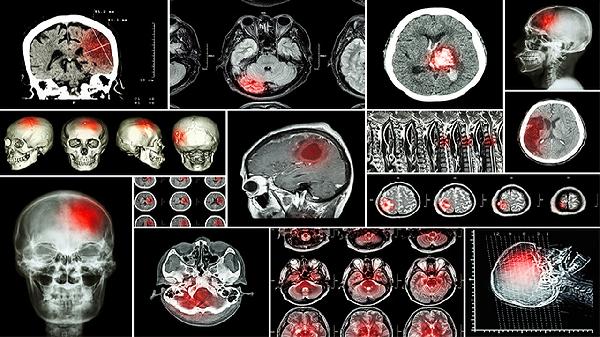

脑血栓形成后6个月内处于恢复期的患者适合服用。药物中的活血成分可促进侧支循环建立,改善病灶周围半暗带区的血流灌注。需注意急性期出血性卒中禁用,使用前应通过颅脑CT明确病灶性质。